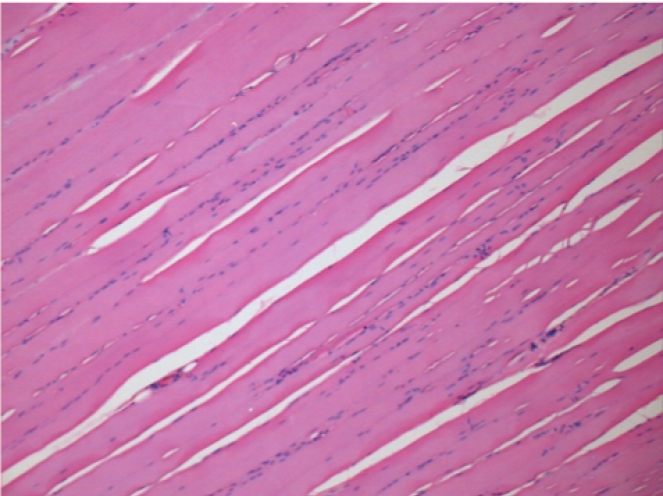

7 mesi dopo Iniezione di Endopeel

Scatola Nr 5

7 mesi (Giorno210) dopo iniezione IM di 0.1ml di Endopeel nel muscolo pretibiale destro ( Dx).

Restitutio ad integrum completo dopo 7 mesi

Sx : Controllo-100x-Giorno210

Dx:100x-Giorno210

Sx :Controllo 50x-Giorno210

Dx:50X-Giorno210